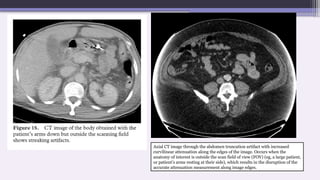

C. Incomplete projections

If any portion of the patient lies outside field of

view, the computer will have incomplete

information relating to this portion and

streaking or shading artifacts are likely to be

generated.

For example a patient is scanned with the arms

down instead of being raised out of the way of

the scan. As the arms are outside the scan field,

they are not present in the image, but their

presence in some views during scanning can led

to such severe artifacts throughout the image as

to significantly degrade its usefulness.

Similar effects can be caused by dense objects

such as an intravenous tube containing contrast

medium lying outside the scan field.

Axial CT image through the abdomen truncation artifact with increased

curvilinear attenuation along the edges of the image. Occurs when the

anatomy of interest is outside the scan field of view (FOV) (eg, a large patient,

or patient’s arms resting at their side), which results in the disruption of the

accurate attenuation measurement along image edges.